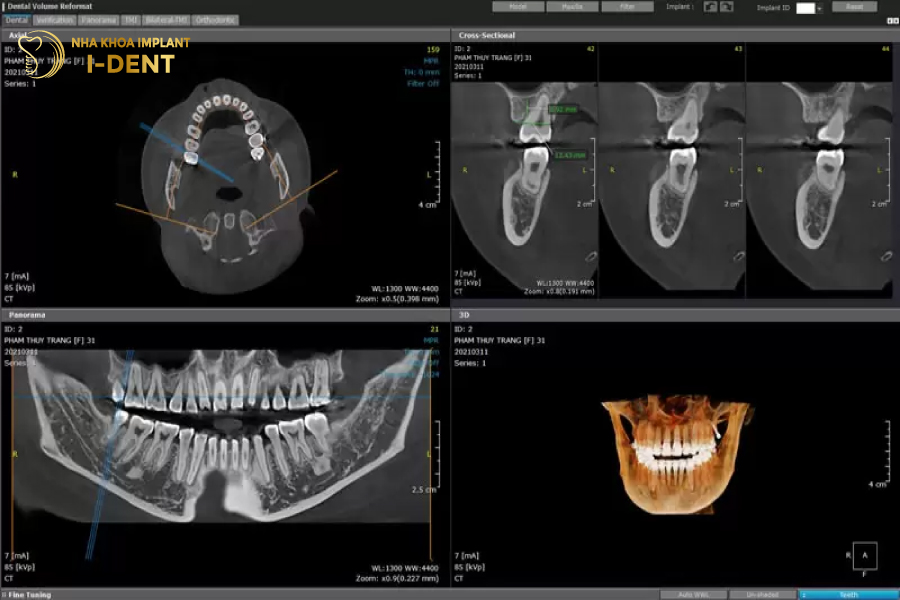

Máy CT Cone Beam thể hiện rõ độ rộng của xương hàm

- Về hiệu quả hiển thị hình ảnh, thì trong khi các máy chụp X – Quang cũ chỉ cho thấy 2 chiều không gian trên và dưới, biết được chiều cao của xương hàm thì CT Cone Beam cho thấy cả chiều rộng và chiều sâu của xương.

Thông qua hình ảnh phim X-Quang 3 chiều, bác sĩ có thể xác định được bề rộng của xương hàm có đủ điều kiện cắm trụ Implant hay không. Hoặc với những trường hợp mất răng lâu năm, gây tiêu xương hàm thì sẽ thông qua phim chụp để xác định cần phải ghép xương, nâng xoang như thế nào. Để Implant tích hợp vào xương hàm không bị đào thải.

Chụp phim CT 3D cũng hỗ trợ bác sĩ trong việc lựa chọn loại trụ Implant có đường kính phù hợp với độ rộng của xương hàm. Đảm bảo trụ răng tương thích với ổ xương, từ đó tích hợp nhanh chóng, ổn định và tuổi thọ lâu dài.

Phim CT 3D sẽ hiển thị rõ mối tương quan giữa răng hàm trên và xoang hàm, để khi bác sĩ cấy trụ Implant sẽ không bị tụt vào xoang hàm. Mối liên hệ giữa răng hàm dưới và các dây thần kinh, để tránh trụ răng chèn ép vào dây thần kinh.

Ngoài ra dựa trên phim CBCT, bác sĩ có thể tính toán được hướng cấy, độ sâu, độ nghiêng khi đặt trụ. Để răng Implant có thẩm mỹ tự nhiên và chịu lực được tốt nhất, mà không bị nứt, gãy trong quá trình ăn nhai.

Tại Nha khoa I-DENT, 100% bệnh nhân thực hiện cấy ghép Implant đều được chụp phim CT 3D trước khi điều trị. Với hệ thống máy Cone Beam CT nhập khẩu trực tiếp từ Mỹ, hỗ trợ bác sĩ I-DENT xác định được cấu trúc vùng răng hàm mặt, mật độ và chất lượng xương hàm. Từ đó chọn được kích cỡ trụ Implant phù hợp, cũng như vị trí đặt trụ chính xác, đảm bảo không chạm vào dây thần kinh.